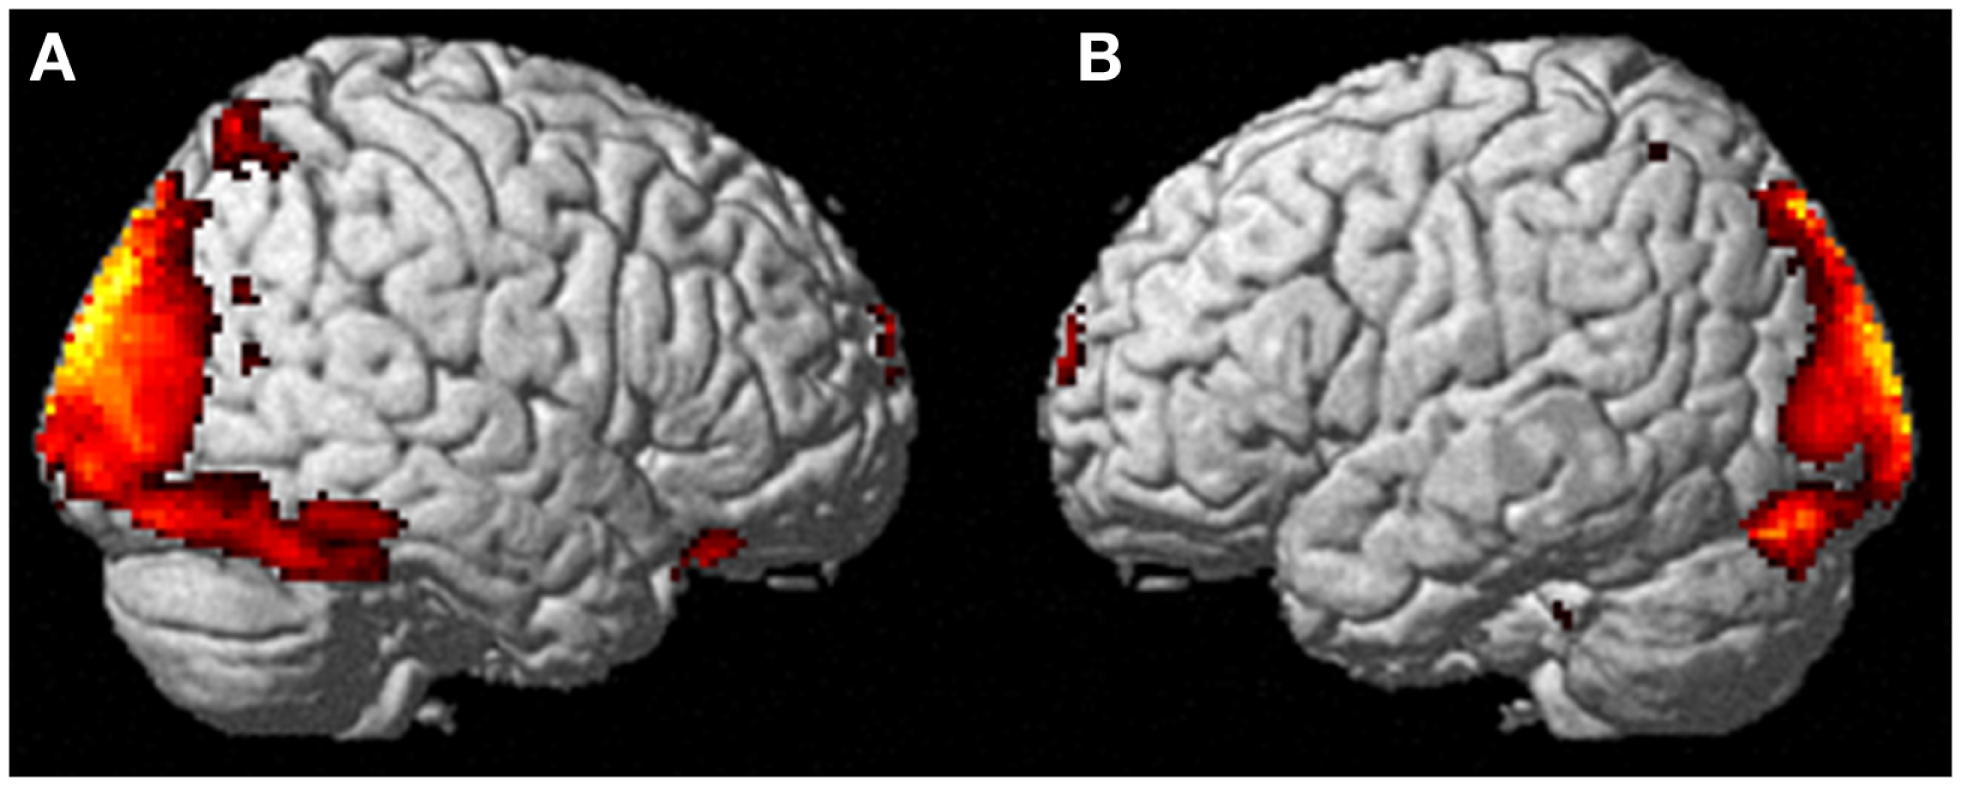

Neural activation patterns for each of these ECE Runs were analyzed separately with rest subtracted from the experience. Given the lack of significant difference between the results of each of the three Runs, all ECE Runs were combined into one analysis to increase power and observe brain regions that were concomitantly activated for each Run. Results are reported with a family wise error (FWE) very stringent correction for multiple comparisons at 0.001. Results are presented in Figure 1. The most significantly and consistently activated areas during the ECE compared to the non-ECE blocks were left lateralized in the supplementary motor area (SMA) (x, y, z = −2, −18, 62, cluster 247, T = 6.66, p = 0.001), supramarginal gyrus/posterior superior temporal gyrus (x, y, z = −64, −46, 24, cluster 60, T = 6.04, p = 0.001), inferior temporal gyrus (x, y, z = −48, −54, −20, cluster 72, T = 5.89, p = 0.001), middle and superior orbital frontal gyri (x, y, z, = −26, 56, −10, T = 5.05, p = 0.001), and the cerebellum (x, y, z = −50, −48, −30, T = 5.76, p = 0.001). The parietal and superior temporal activation taken together correspond to the temporal parietal junction. There was significantly less activation during the ECE blocks compared to non-ECE blocks (Figure 2) in bilateral posterior visual regions: the lingual gyrus (x, y, z = 14, −64, 4, cluster 19205, T = 13.23, p = 0.001) and the cuneus (x, y, z = 0, −92, 18, cluster 19205, T = 12.71, p = 0.001).

Figure 2. Areas of reduced activity during the ECEs compared to rest. The visual cortex is particularly impacted. (A) Representation of the right side; (B) activity on the left. The p-value for this image was set at 0.05 FWE corrected.

During imagining herself moving as she did in the first ECE (Run 1), without inducing an ECE, controlling for multiple comparisons at a p < 0.001, the participant activated more left cerebellum (x, y, z = −46, −48, −44, cluster 406, T = 5.66, p = 0.001) and bilateral lingual gyrus (x, y, z = −14, −62, 6, cluster 980, T = 5.00, p = 0.001; x, y, z = 6, −58, 8, cluster 790, T = 4.82, p = 0.001) than when imagining someone else moving in the same way (Figure 3). Similarly, she showed significantly less activity during self-imagining than imagining someone else in the bilateral superior orbital frontal gyrus (x, y, z = −18, 66, −2, cluster 148, T = 4.40, p = 0.025; x, y, z = 14, 68, −2, cluster 146, T = 4.38, p = 0.026).

Figure 3. Results from visualizing herself doing the same action she performed in the first ECE vs. visualizing another person performing the same movement. (A) Bilateral lingual gyrus differences in activity and (B) the left cerebellar differences. The p-value for this image was set at 0.001 uncorrected.

The ECE was reported as a mixture of visual imagery and kinesthetic imagery but the kinesthetic component was prominent as evidenced by the report of feeling dizzy when performing a rotational movement. The prominence of kinesthetic experience over the visual experience is consistent with a strong bilateral deactivation of the lingual gyrus and cuneus encompassing the primary visual cortex. Activations are mainly left-sided and involve the left SMA, supramarginal and posterior superior temporal gyri (the last two overlap with the temporal parietal junction, which has been associated with out-of-body experiences). The cerebellum also shows strong activation that is consistent with the participant’s report of the impression of movement during the ECE. There are also left middle and superior orbital frontal gyri activations, structures often associated with action monitoring.